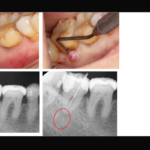

【5ヵ所の穿孔と根尖部の破折器具を伴う下顎左側第二大臼歯の症例】「近医で抜歯と言われたが、歯を残したい。」

「近医で抜歯と言われたが、歯を残したい。」とのことで来院された患者様の症例です。